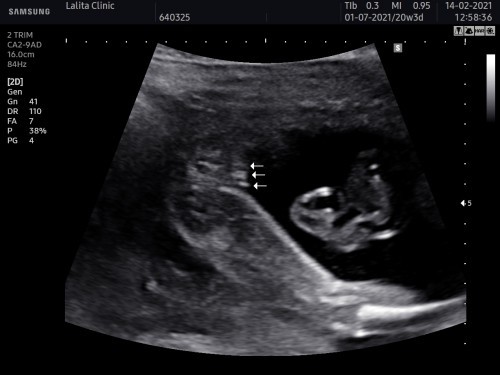

หญิงค่ะ ดูจากรูปสอง เพราะคว่ำลง ถ้าชี้ขึ้นจะเป็นชายค่า

หญิงนะคะแม่ ของเราแบบนี้เลยหมอบอก เป็นสามเส้นชัดเจน

มีกลีบ หญิงนะคะ